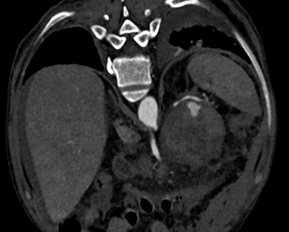

The patient was hemodynamically stable, but with mild tachycardia. He underwent endovascular embolization treatment, in which he was selectively catheterized in the splenic artery and dorsal pancreas (Figure 2). Lipiodol and a controlled-release spring were used to occlude the pseudoaneurysm and dorsal pancreatic artery, maintaining patency of the splenic artery (Figures 3 & 4). At the end of the procedure, there was no extravasation of contrast. During hospitalization, the patient remained in an intensive care bed for 48 hours for hemodynamic surveillance and clinical treatment of post-contrast acute renal failure. The patient was discharged 96 hours after the procedure. Being guided at every hospital discharge to follow up in the outpatient service.

Figure 2 Endovascular embolization treatment, show selectively catheterized in the splenic artery and dorsal pancreas.